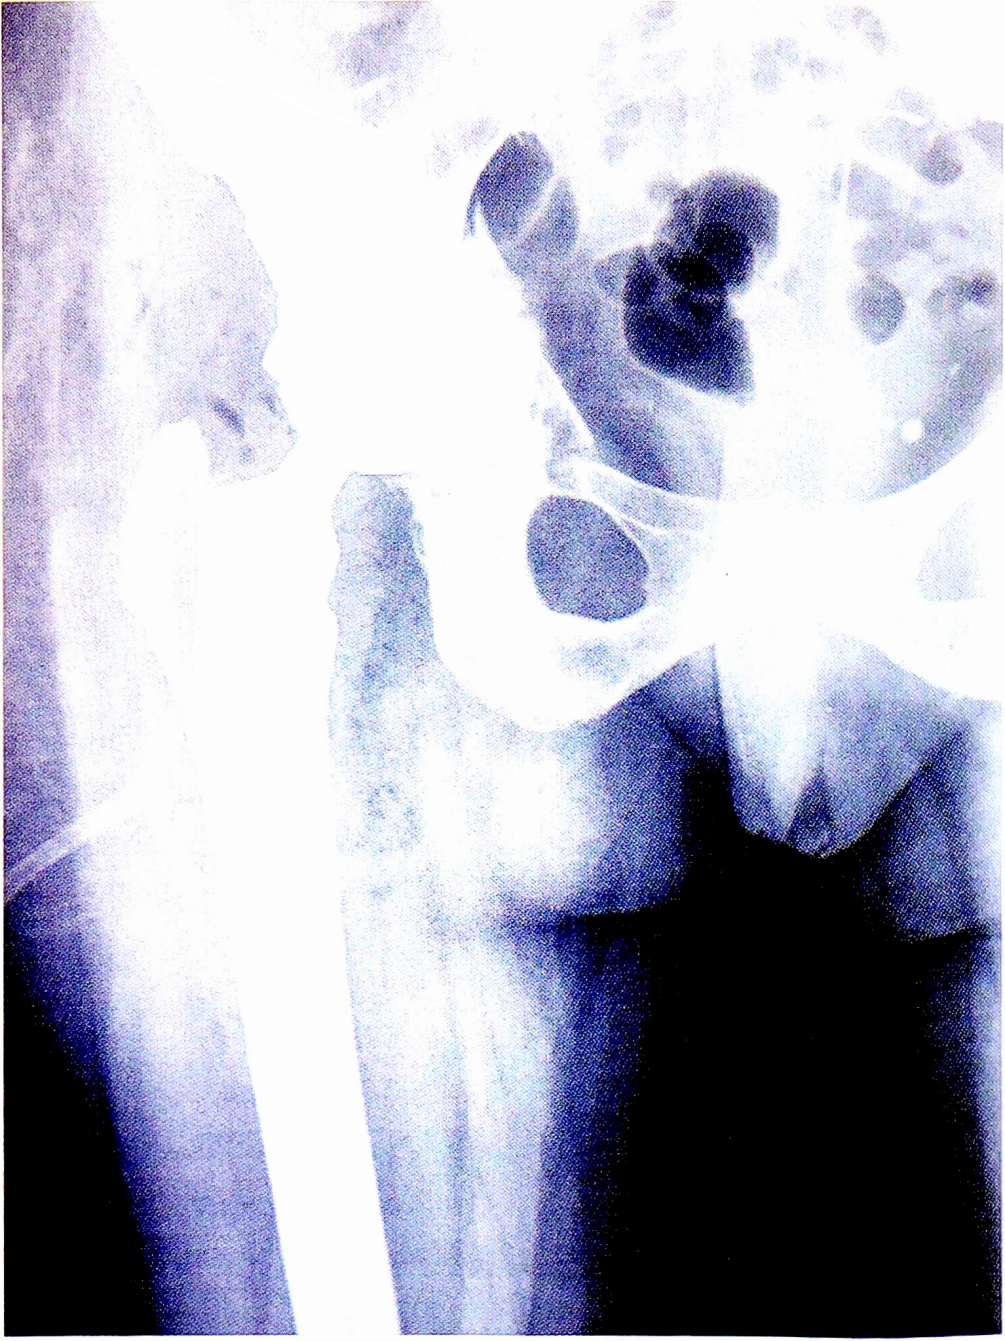

Данный клинический случай (рис. 3) демонстрирует компромиссный путь для уменьшения времени оперативного пособия и объема кровопотери за счет отказа от расширенной остеотомии большого вертела или бедренной кости, необходимой для вынужденного удаления стабильного остеоинтегрированного бедренного компонента. Последнее было бы крайне нежелательно не только из-за лишней травматизации, но и учитывая молодой возраст пациентки (никогда не известно, сколько будет служить новый бедренный компонент, так как известно, что каждая дополнительная замена ухудшает качество кости и прогноз выживаемости имплантата).

Рис. 3. Рентгенограмма той же пациентки после ревизионной операции.

Fig. 3. X-ray of the same patient after revision surgery.